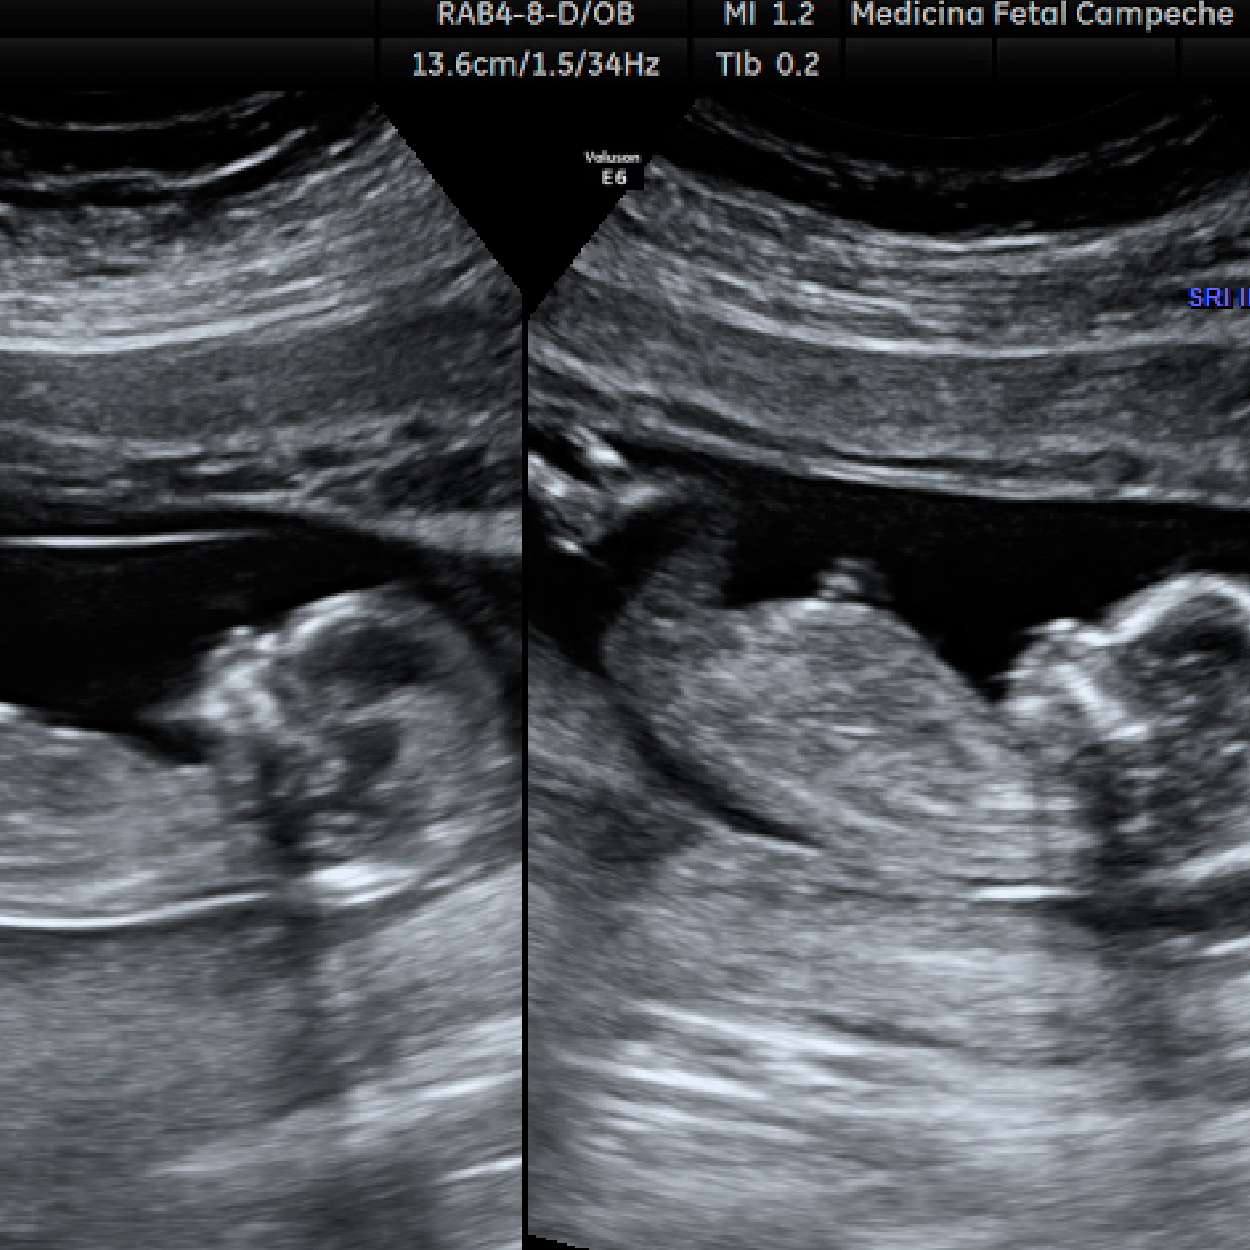

El ultrasonido es una técnica de diagnóstico por imagen; generada por de ondas de sonido que viajan a través de tu pancita, estas ondas de sonido son inofensivas para tu bebé, y nos permiten "fotografiar" y medir varias estructuras en formación.

El ultrasonido durante el primer trimestre del embarazo por lo general se hace para evaluar la ubicación del embarazo y forma parte de un examen tanto obstétrico (embarazo) como ginecológico (evaluación de matriz y ovarios).

7. Evaluación del saco gestacional y del embrión antes de las 10 semanas.

8. Evaluación anatómica del feto después de las 11 semanas (preferentemente 12-14 semanas).